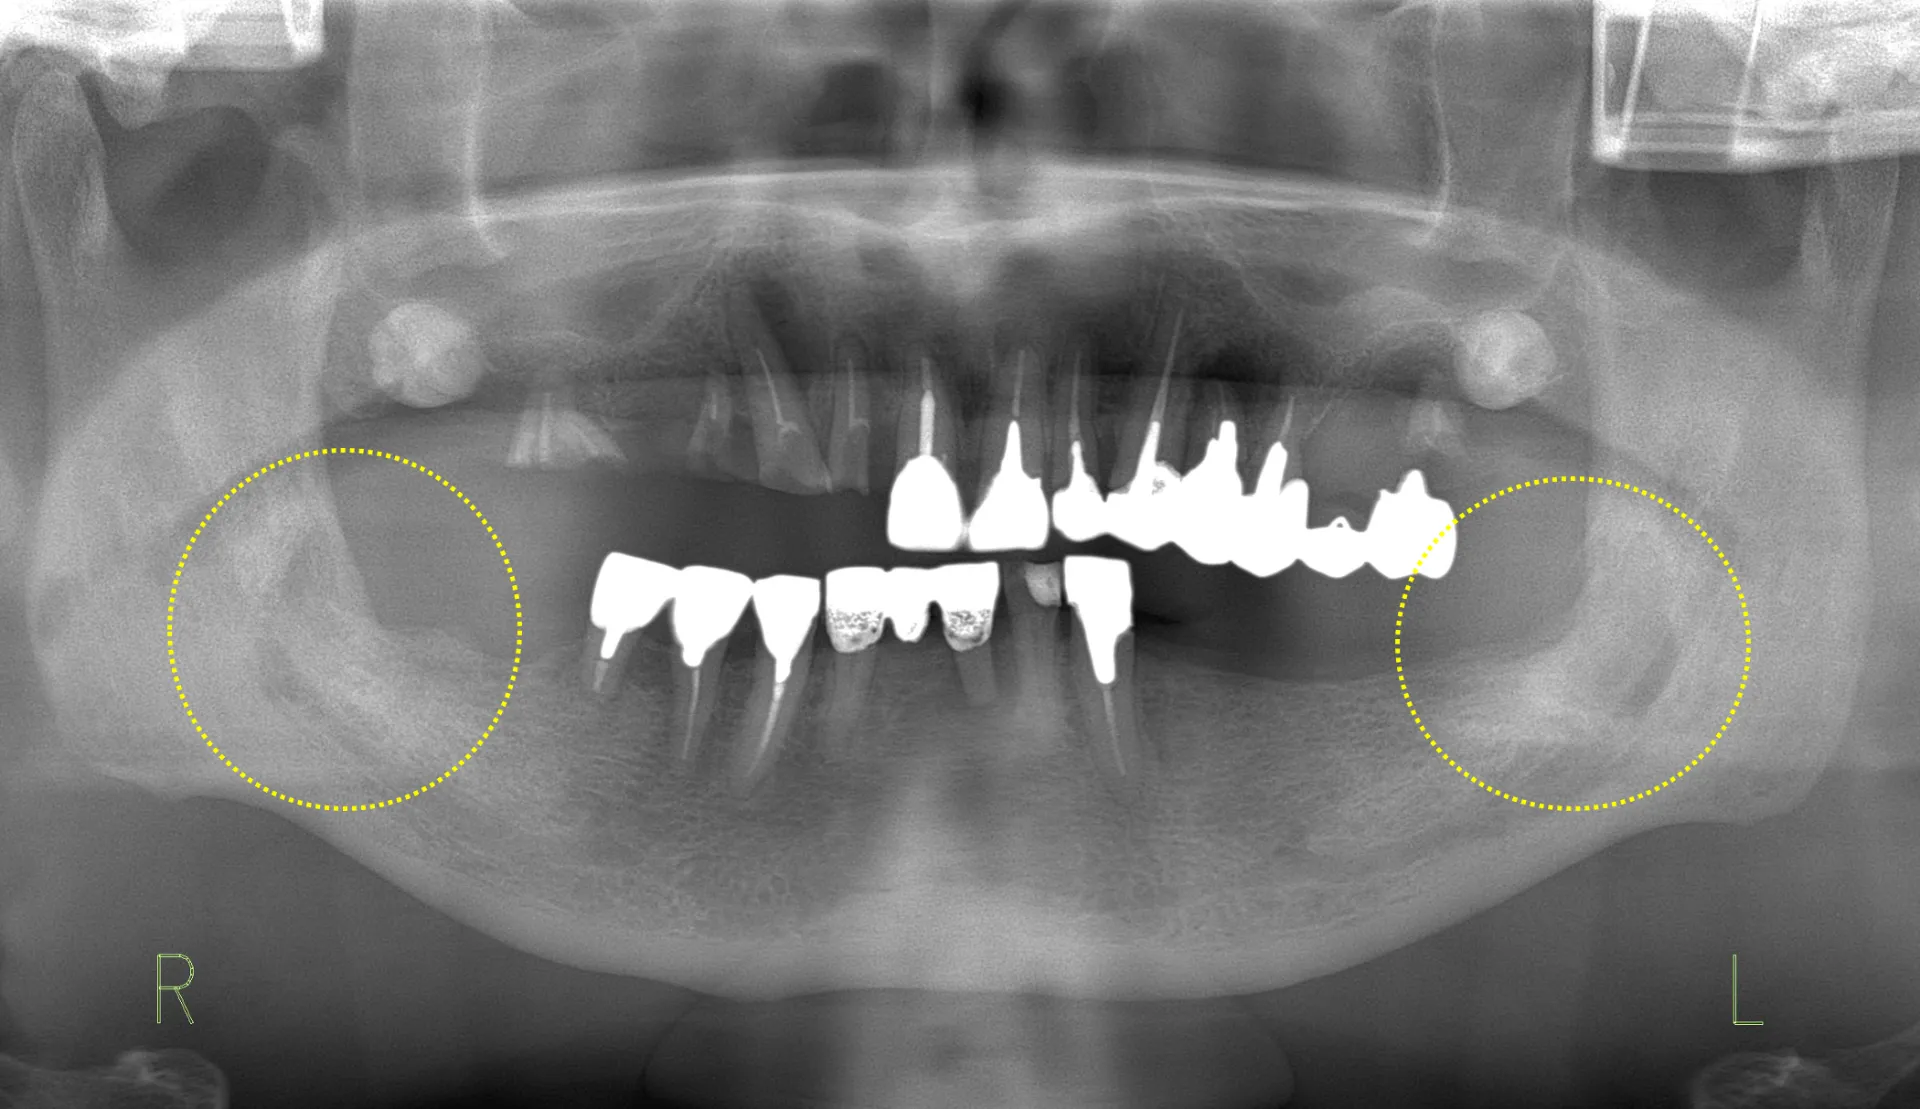

左右下8:含歯性嚢胞